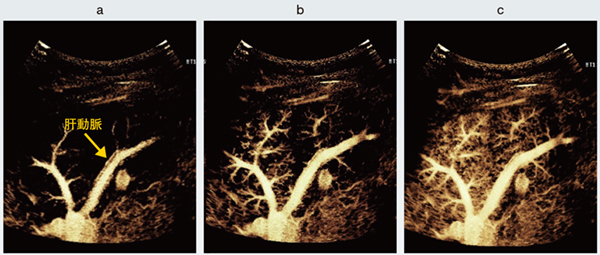

〔Super Resolution MVIの臨床画像〕

図1 正常肝実質のSuper Resolution MVI画像

門脈の末梢が精緻に描出されており,門脈に並走する肝動脈も明瞭に分離して観察される。肝実質が時間の経過とともに規則的かつ均一に染まり,正常な肝血流動態を反映している。

a:Flash後1秒 b:Flash後3秒 c:Flash後7秒

図2 Super Resolution MVIによる肝腫瘍の血管構築パターン

a:転移性肝がん b:肝細胞がん c:限局性結節性過形成